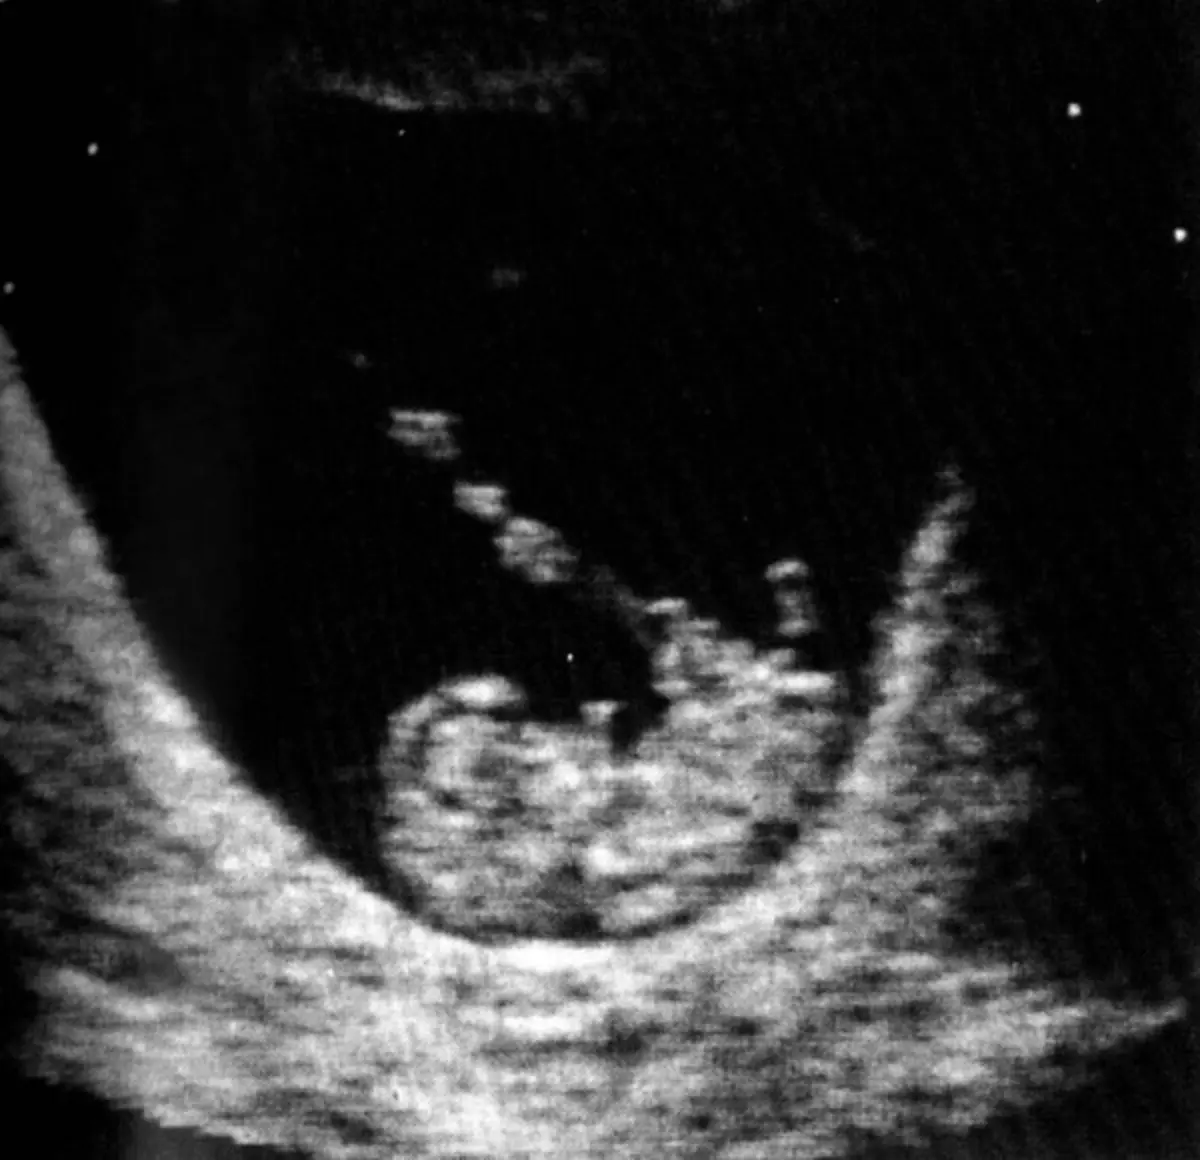

Não foi detetada uma malformação grave numa ecografia morfológica

Segundo uma notícia divulgada pela SIC no fim de semana, foi na clínica do Pinhal Novo (Setúbal) que a ecografia morfológica foi feita em 2023, não tendo sido detetada uma malformação grave num feto. O bebé nasceu com a perna direita incompleta.